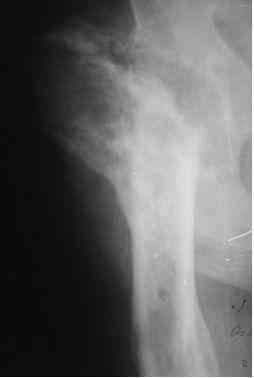

Анамнез: в 1992 г. оперирован в РНЦ «ВТО» по поводу ложного сустава шейки правого бедра (Р-снимок в приложении), 1994 перенес инсульт с исходом в правосторонний гемипарез. Передвигался без костылей, имея укорочение этой конечности на 3,5 см, порочную сгибательно-приводящую установку правого бедра и ДОА правого коленного сустава III ст. с перегрузкой латерального компартмента. Имеются дегенеративно-дистрофические изменения в поясничном отделе позвоночника. Больной до последнего времени «таксовал» на своей машине. 23 дня назад, поскользнувшись, упал в своей квартире, получил 2-х лодыжечном переломе костей правой голени с подвывихом стопы кнаружи (Р-граммы правового коленного и г/стопного суставов прилагаются). Помощь оказана в городском травмпункте г.Темиртау (Казахстан) Лечился гипсовой шиной, как рассказывает больной манипуляций на г/стопном суставе не проводили, посчитали, что все в порядке. Мое мнение - для создания опорной конечности необходимо произвести первичный артродез.Попов Виктор, г.Караганда.